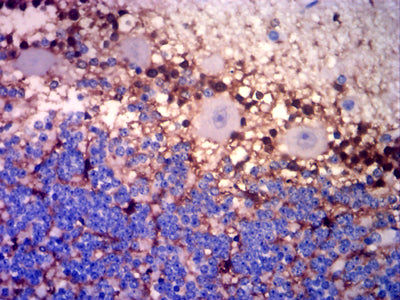

Immunohistochemical analysis of paraffin-embedded human cerebellar tissues using GLUL mouse mAb with DAB staining.